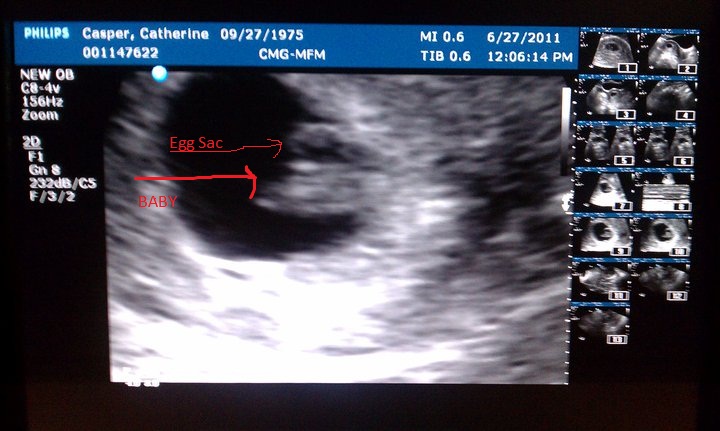

Wes and I are expecting our second baby.  All my blood work up came back today as excellent.  And I had an ultrasound this past Monday.  Baby is progressing, perfectly.  I was able to see the heart beating on the monitor and it was amazing!  152 beats a minute.  Very strong and healthy!  I just wish the stomach sickies would end and my vertigo would go away.  Other then that, it's been okay.  LOL Due on Feb. 14th, 2012. Yes, Valentine's Day! |